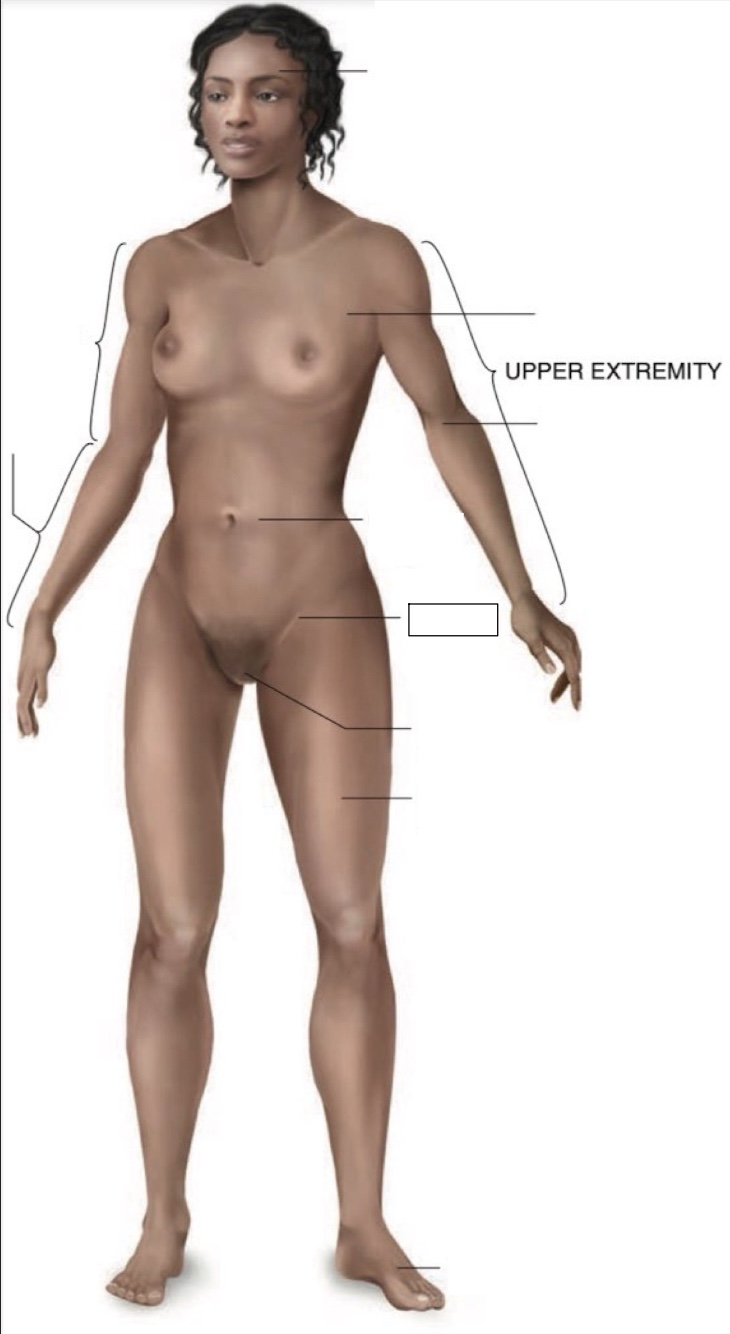

inguinal region